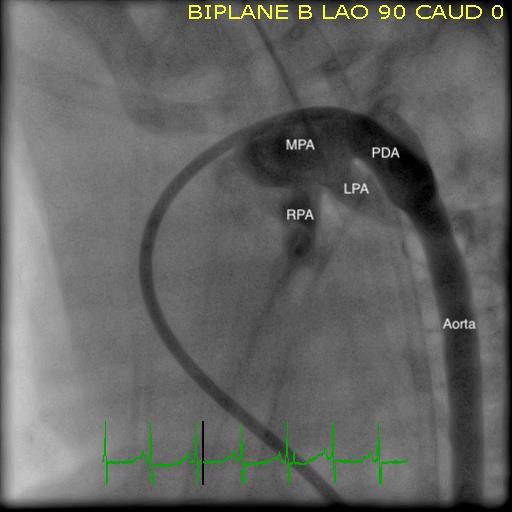

Angiograms from a PDA closure procedure in a preterm infant. Left: Baseline. Right: After closure. The patient was a 900-gram 24-week preterm infant. MPA: Main Pulmonary Artery; LPA: Left Pulmonary Artery; RPA: Right Pulmonary Artery; PDA: Patent Ductus Arteriosis.

Dr. Goldstein’s substantial clinical experience will allow UPMC Children’s to develop a robust PDA closure program in preterm neonates. The ability to offer this patient population access to a much less invasive procedure — with lower rates of complications and postprocedural morbidities in a catheter-based, short procedure — stands to greatly improve care in select patients for whom the procedure can benefit.

“We now have the tools and technology to transition most of these patients who require PDA ligation to transcatheter device closure via a short procedure. The first catheterization procedure that I performed after arriving at UPMC Children’s was a PDA closure on the smallest patient ever treated in the catheterization laboratory here — just under 800 grams,” says Dr. Goldstein.